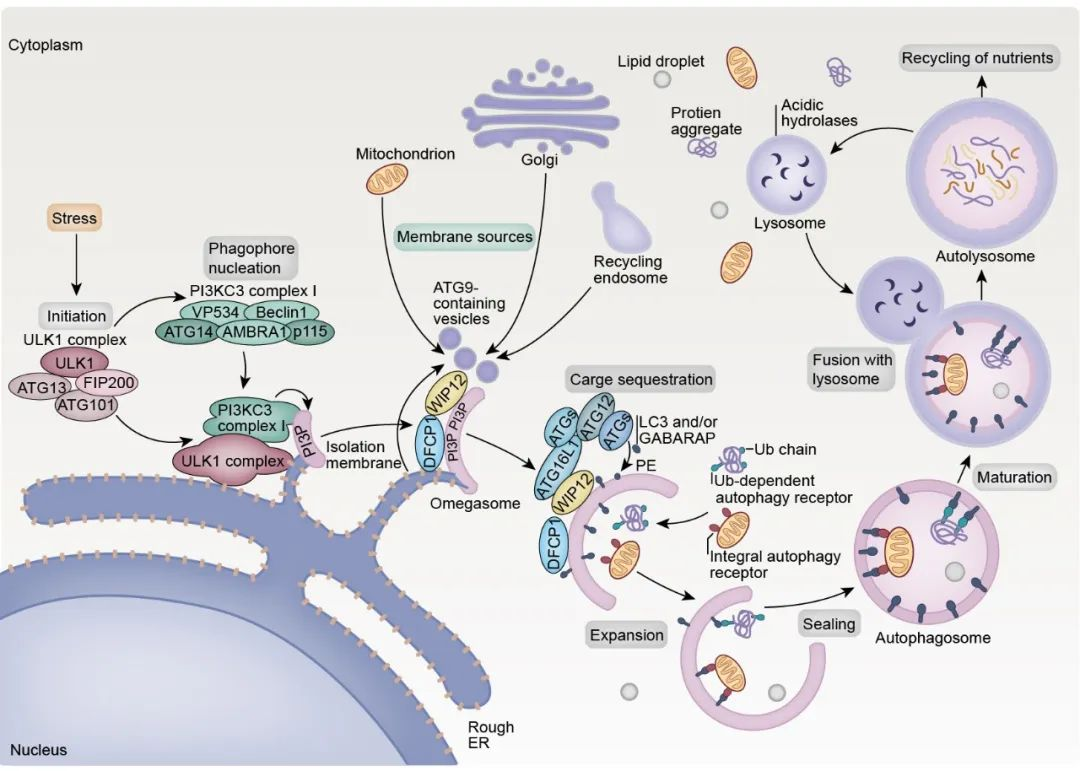

论文插图设计

滑动查看更多 点击查看大图